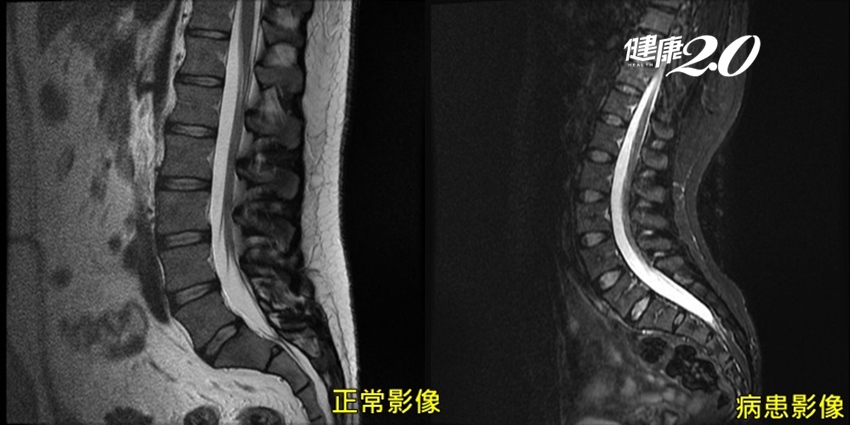

而王小姐屬於更罕見的一群,其核磁共振影像與正常人幾乎相同,經透過肌電圖檢查,患者的肌肉狀況正常,術後當神經傳導恢復,有一半的機率能夠改善6至7成腿部的狀況,雖可能無法如一般人正常跑跳,至少可以不再為腿麻腿疼、夜夜失眠、大小便失禁所苦。

▲從影片中可以看出王小姐的脊椎明顯的異常。